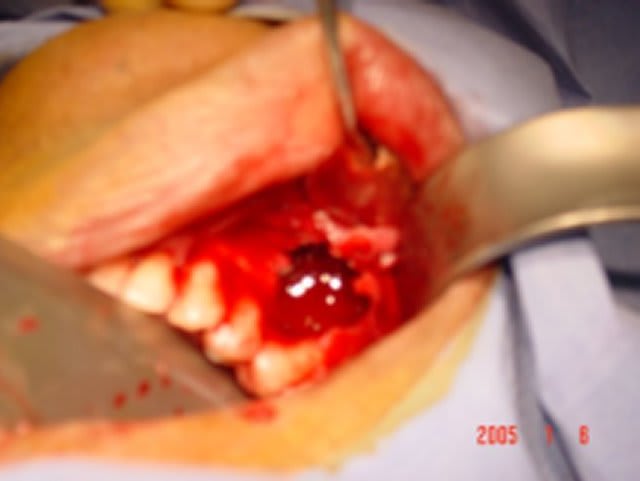

desole mais ls p^hotos sont pas top ;la panseuse est meilleur IBOD que photographe

j'ai demande au dentiste qui s'occupe de la patiente de realiser les endo avt la chir malgres le fait qu'elle avaient conservé leurs vitalité

a ce jour elle sont encore en place mai la 45 risque de sauter si dans 3 semiane je n'ai pas une meilleur stav*bilite transversale

si tu regarde le scanner tu verras que le foramen mentonnier a ete completement repousse au niveau du rebord basilaire par le kyste (desole je ne sai plu quelle numero de photo )

j'ai pu donc realiser un lambeau de pleine epaisseur de 43 a 47 avec incision de decharge en mesial de 43 puis arrive au niveau du rebor basilaire j'ai disseque en epaisseur partiel.

au niveau du kyste j'ai decolle la membrane kystique en mesial distal lingual vestibulair emais pas en apical puis avec une pince hemostaqtiue tu tires doucement et il veint en un gros morceau .

ensuite tu as un acces visuel sufisant pour te permettre de nettoyer la partie apical en respectant le nerf alveolaire

une fois visualise ce n'est pas difficile de ne pas l'abimer